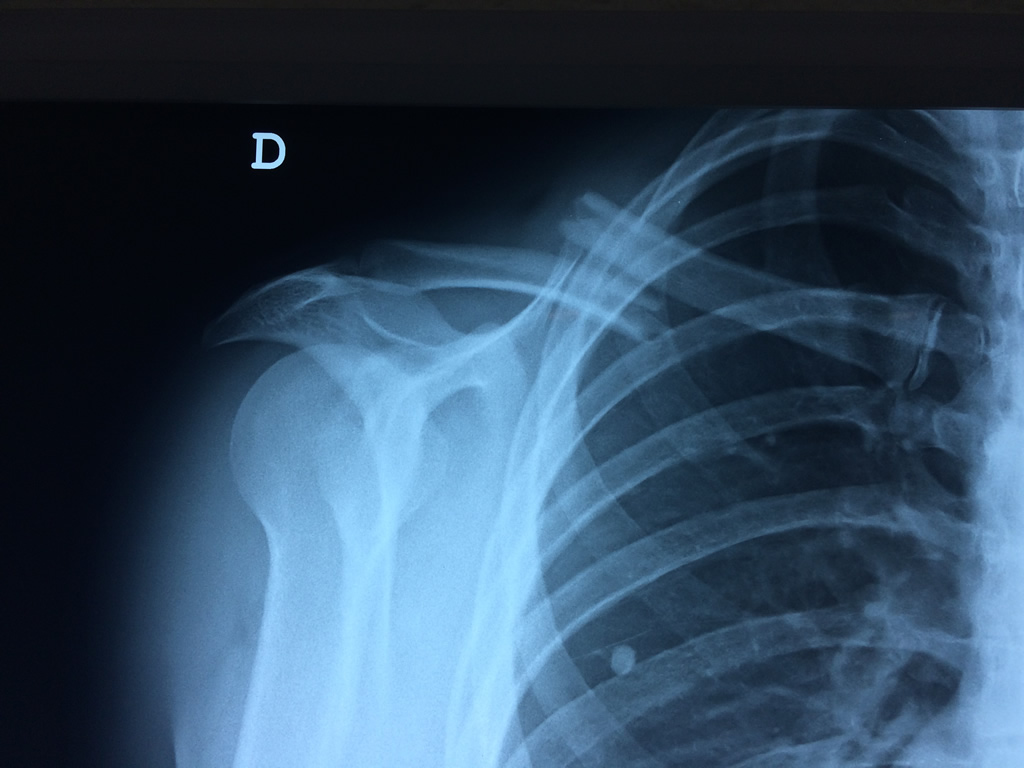

Clavicula 2

Detail Download